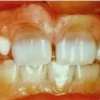

Tetratsükliini liigtarbimise tõttu värvunud hambad

Emaili hüpoplaasiad

– Hammaste krooni kaltsifitseerumise häired, emaili hüpoplaasiad, on üsna sagedased. Need on nähtavad vahelduvate värvi- ja ehituse muutustena hamba pinnal.

– Hüpoplaasia on tingitud emaili tootvate rakkude normaalse talitluse häirumisest, mida tavaliselt

põhjustavad välised tegurid (näit. nakkused).